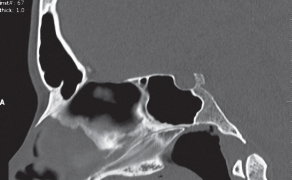

Streszczenie: Pacjenci z częściowymi brakami uzębienia są grupą osób, u których obserwuje się spontaniczne wydłużenie zębów w łuku przeciwstawnym do luki. Tego typu zaburzenie płaszczyzny okluzyjnej może uniemożliwić wykonanie odbudowy protetycznej lub zmusić do radykalnego szlifowania zębów pod stałe konstrukcje protetyczne. Jednym z rozwiązań tego problemu klinicznego może być ortodontyczna intruzja wydłużonych zębów.

Intruzja zębów jest zadaniem trudnym, ponieważ w przypadku stosowania konwencjonalnych aparatów występuje ryzyko niepożądanej ekstruzji zębów stanowiących jednostkę kotwiącą. Zastosowanie zakotwiczenia szkieletowego pozwala uniknąć tego efektu ubocznego.